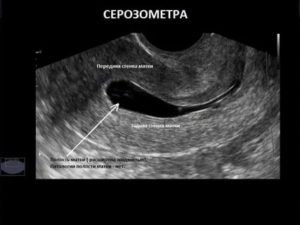

Чтобы выявить скопление жидкости, обязательно ультразвуковое обследование. Только оно способно точно определить серозометру.

Серозометра – это женская патология, при которой у пациентки наблюдается свободна жидкость в полости матки. Между мышцами детородного органа и эндометрием расположена серозная мембрана.

Что делать, для обнаружения патологии? Существует ряд заболеваний, которые по своей симптоматике очень похожи между собой. Для выявления серозометры используются такие методы диагностики, как УЗИ и гинекологический осмотр.